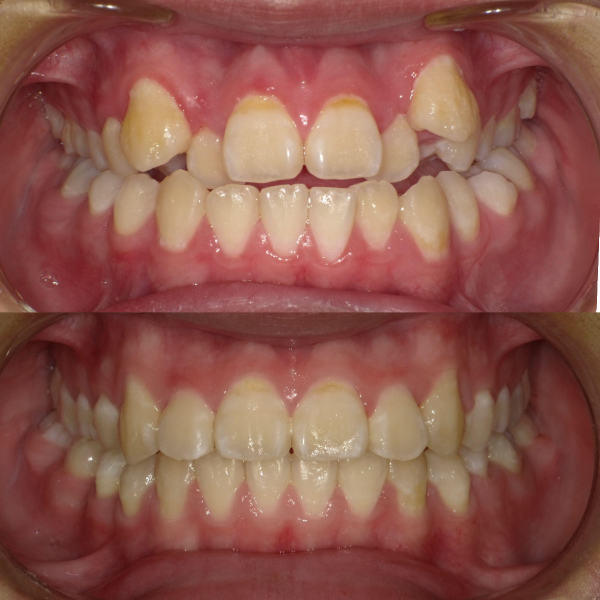

そういった様々な要因を取り除くことで、従来、小臼歯(4番、5番)を抜歯しなければ治療できない症例でも、非抜歯で治療可能となってきているのです。

機能的に小臼歯は非常に大切な歯であることから、最大限小臼歯を抜歯せずに治療できる治療方針を考えます。

また、下顎の位置関係、歯の傾きなどの原因を新素材ゴムメタルワイヤーで治療を行うことでほとんどの症例で小臼歯を抜歯しなくても治療可能になってきています。